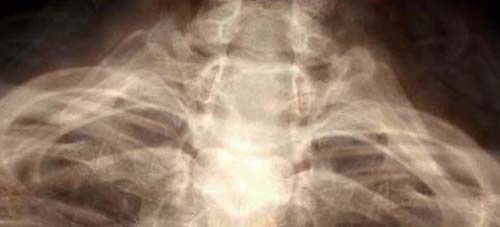

2003: As the body becomes fragile, what becomes of the self?

These images were shown in my MFA Thesis show at the Mass College of Art. In the first six images, I used the computer to combine my medical records with x-rays. The edges were created by encouraging the ink to run. The other four images are my x-rays that were modified in the computer and then printed large (2' x 4'). All images are inkjet prints on Vellum.